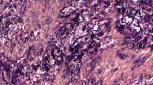

Giemsa-stain_Dog-Skin-Tumor